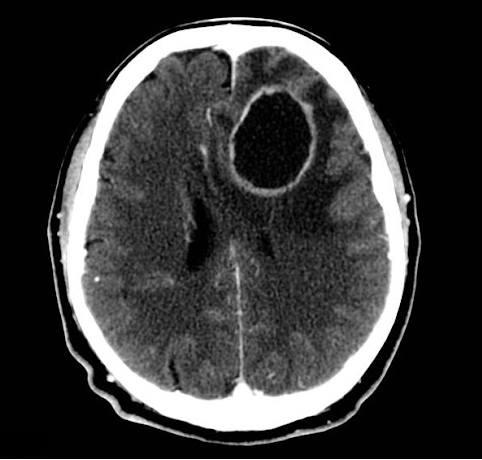

Рамолиционные кисты (от размягчения) образуются в местах некроза после кровоизлияния, воспаления или инфаркта. Происходит размягчение, рассасывание мертвых тканей с формированием полости – ложная киста, стенка которой состоит из тканей самого органа. Часто такие кисты образуются после инсультов.

В большинстве случаев кисты бессимптомны и обнаруживаются случайно. Клинические проявления обычно связаны с ростом кисты или ее расположением. Например, маленькая киста в почке может никак не проявляться, а в головном мозге приводить к головным болям, эпилепсии. С другой стороны, по мере роста киста почки нарушает ее работу, приводя к повышению артериального давления, развитию почечной недостаточности.